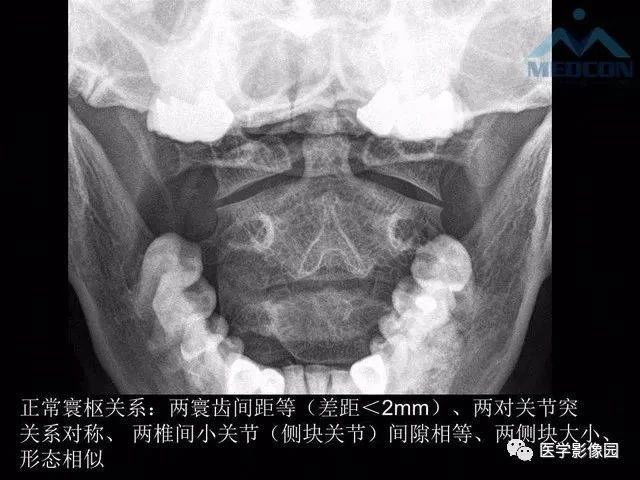

01正位片

观察有无寰枢关节脱臼,齿状突骨折或缺失(张口位片);第七颈椎横突有无过长,有无颈肋。钩椎关节及椎间隙有无增宽和狭窄。